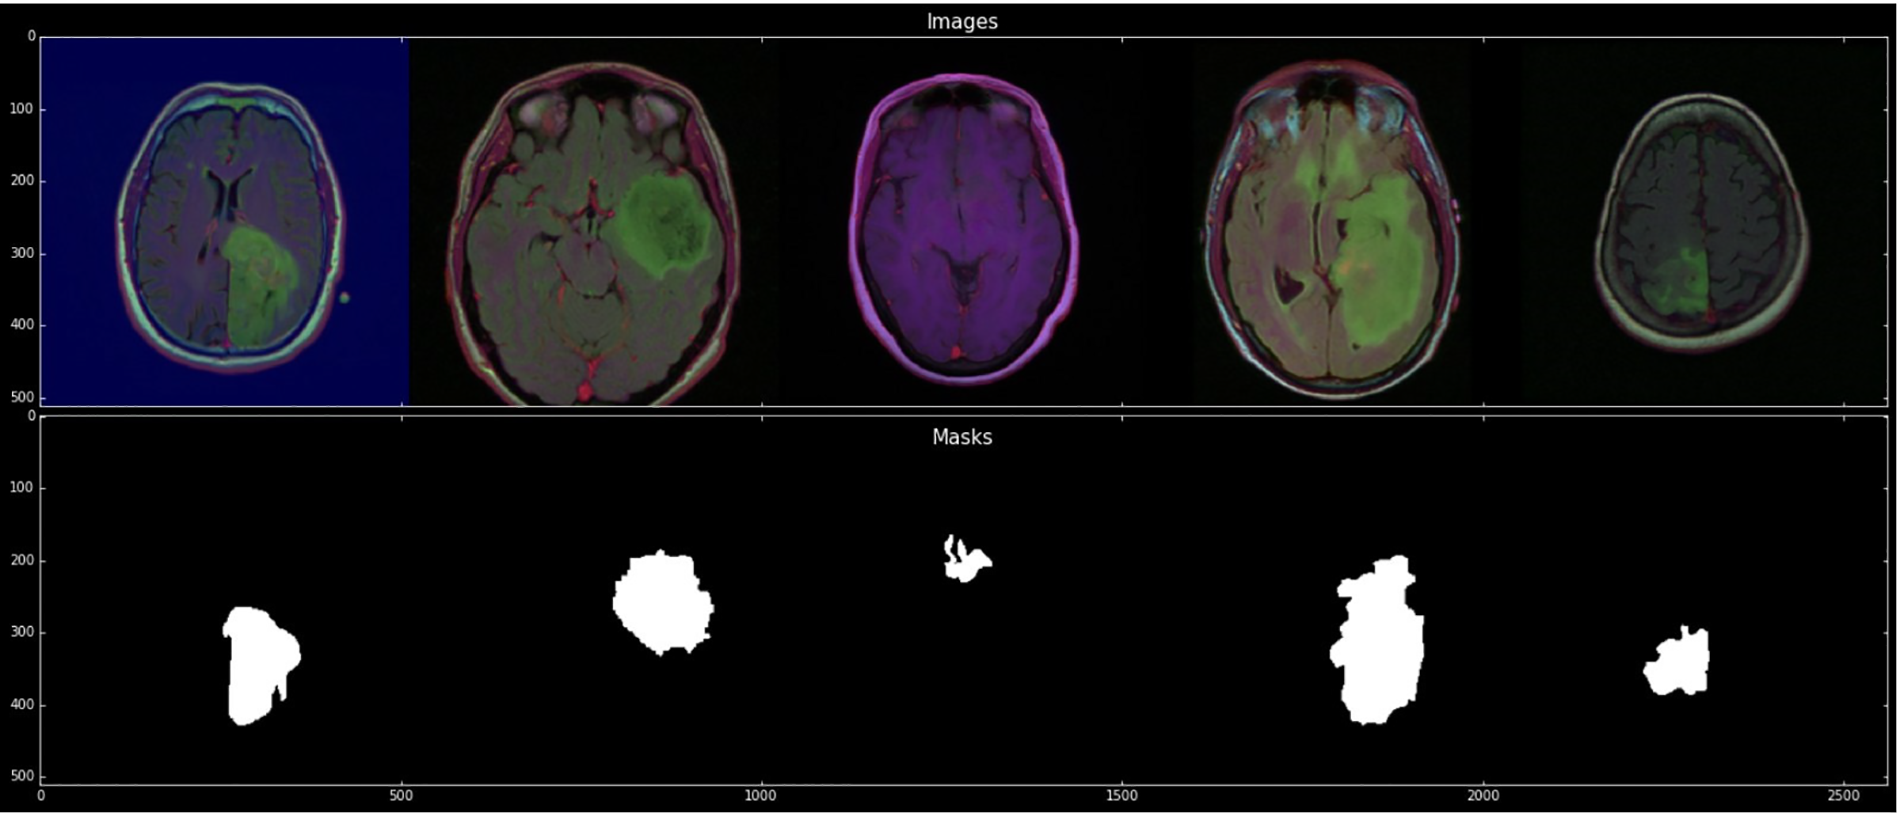

Each cluster contains five patients. The process was completed for the evaluation with a cross-validation technique. The imaging dataset used in our research work was captured from Imaging Archive. Sample images with their mask are shown in Fig. 2. This dataset consists of the patients’ images related to TCGA and subsidized by the National Cancer Hospital. We used all the treatments when available, but when one was not, we only used FLAIR. Six patients lacked the pre-contrast sequence, nine lacked the post-contrast sequence, and 101 had all the relevant series. The resource has published all of the patients’ information in total 1. Among 20 to 80 patients received the number of slices. We only looked at bilateral data to detention the initial pattern of tumor progression. The genomic dataset used in this investigation included measurements of the IDH mutation 1p/19q co-deletion and DNA methylation, gene expression, DNA copy number, and microRNA expression. We consider six previously discovered genetic classifications of LGG in our research, which are known to be connected with some tumor form aspects.

Figure 2: Sample images with mask